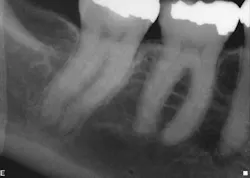

When the anatomy is more complicated than can be predictably treated with WaveOne, but not so irregular as to require all of the files of Vortex Blue, is there another option? It is in these clinical situations that ProTaper Next® (Dentsply Tulsa Dental Specialties) becomes the best file system (Figs. 5 and 6). The rectangular but off-center cross-section creates the illusion that the canal is slightly larger than it is because the alternating contact points of the file prevent the feeling of the file getting locked into the canal space. This added space along the file results in additional room for debris removal, and in spite of this design, there is no appreciable loss of cutting efficiency. When using ProTaper Next files to create the final root canal shape, two or three instruments will be used.

Fig. 5: With a crown in place, it can be difficult to determine the size of the pulp chamber. However, at the level of the roots, the canals in tooth No. 3 look to have calcified compared to the neighboring teeth.